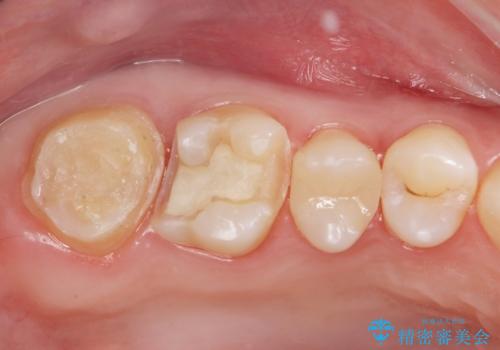

奥歯の虫歯の治療

- 奥歯が虫歯になっていたため治療しました。

手前側の歯は前から見えるため、セラミックの詰め物で治療しました。

奥は高さを取るのが難しかったため薄く作れる金属(ゴールド)で治療しています。

- 合計 26.4万円(内訳:右上7 PGAクラウン 11万円(旧料金)、右上6PGAインレー 7.7万円(旧料金)、右上5 emaxインレー 7.7万円)費用は治療当時の料金となります